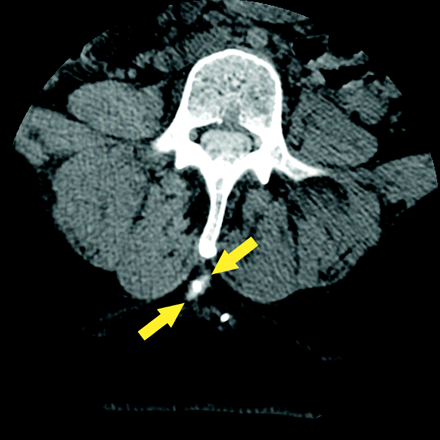

CT

To our knowledge, there is scant literature regarding the use of CT in the evaluation of ITB pump malfunction. Our institutional experience, however, suggests that CT—particularly postcontrast (ie, postinjection of contrast material through the accessory pump port) CT—can be a useful adjunct to fluoroscopy performed during contrast injection for improved identification and characterization of leaks and fluid collections (Figs 8–10).40 Cross-sectional imaging can also aid in visualizing the location of the catheter tip in the spinal canal (ie, within the intrathecal sac) when plain film findings are equivocal (Fig 11).34,41 Two-to-three milliliters of myelographic contrast agent can be injected through the accessory pump port (after successful CSF aspiration) and should be performed while the patient is on the CT table to ensure that the contrast is not overdiluted in the CSF when the images are acquired.34 At our institution, we inject as much as 5–10 mL of thecal sac−compatible contrast material while observing the entire pump-catheter system fluoroscopically and then immediately obtain a CT scan of any areas of concern. Dependent layering of contrast material in the IT space adjacent to the catheter tip suggests a normal study finding. Contrast collection in the subcutaneous, subdural, or epidural spaces suggests leak or tip migration. Limited accumulation of contrast material near the catheter tip with the contrast not appropriately layering in the IT space may suggest focal loculations within the subarachnoid space in the region of the catheter tip.34

Axial CT image demonstrates an extraluminal contrast collection (yellow arrows) adjacent to an apparently intact catheter. This contrast extravasation was not identified at fluoroscopic evaluation performed during contrast injection.